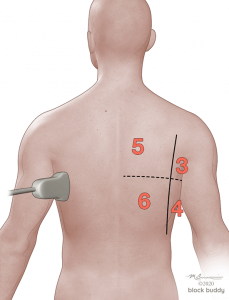

4. Positioning and Scanning

- Scanning can be performed with the patient in a supine, lateral or sitting position.

- In the critically ill patient, perform the scan with the patient supine and modified lateral position.

- When evaluating for a pneumothorax, perform the scan with the patient in the supine or semi-recumbent position.

- Use the anterior axillary (AAL) and posterior axillary (PAL) lines to divide each hemithorax into an anterior, lateral, and posterior zone.

- Further divide each zone into a superior and inferior region by drawing an imaginary horizontal line.

- This will create 6 zones over each hemithorax.

- Initially place the transducer in the long axis over zone 1.

- Reposition the transducer over each subsequent zone to complete the evaluation.

- COVID-19 ultrasound findings (B-lines, consolidations, air bronchograms, and pleural abnormalities) are most commonly seen in the posterior lower fields of both lungs.

- Ultrasound findings (B-lines, consolidations, air bronchograms, and pleural abnormalities) are most commonly seen in the posterior lower fields of both lungs.